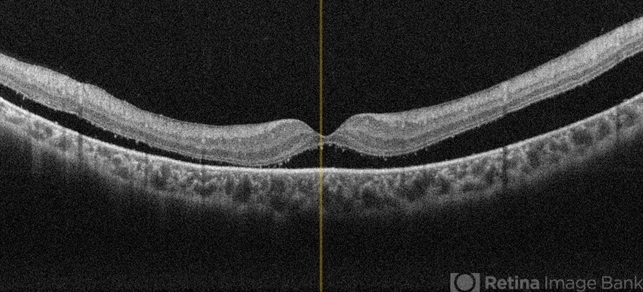

- OCT, left eye, subclinical detachment, retinitis pigmentosa

- OCT of a 6 year old male child showing subretinal fluid with macula off in a case of subclinical RD in retinitis pigmentosa.